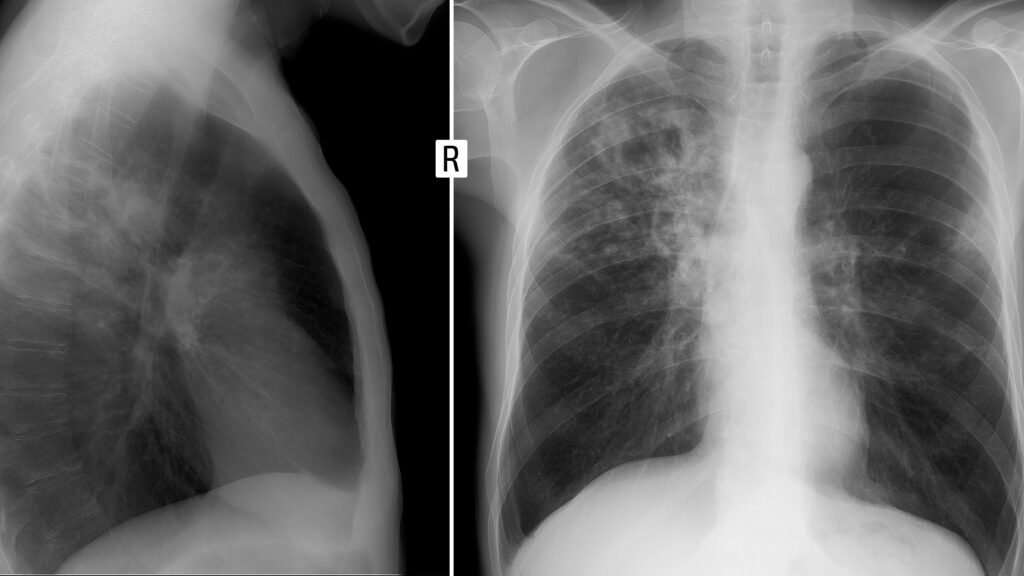

Home Prototypes Is AI ready to interpret chest X-rays without human supervision? Prototypes Is AI ready to interpret chest X-rays without human supervision? By styloux - December 8, 2025 22 0 FacebookTwitterPinterestWhatsApp In radiology, an early adopter of health AI, a debate is brewing: Should generative AI models interpret medical images on their own? RELATED ARTICLESMORE FROM AUTHOR Prototypes Commonwealth Bank to Cut More Jobs Amid Broader AI Push Prototypes Trump administration vows crackdown on Chinese companies ‘exploiting’ AI models made in US Prototypes One New Thing: Outside-the-Box AI Education for All Prototypes The Best Artificial Intelligence (AI) Growth Stocks on the Nasdaq That Wall Street Loves Right Now Prototypes Opinion | Notable & Quotable: Artificial Intelligence Prototypes A museum dedicated to artificial intelligence-driven art opens in downtown LA this summer LEAVE A REPLY Cancel reply Please enter your comment! Please enter your name here You have entered an incorrect email address! Please enter your email address here Save my name, email, and website in this browser for the next time I comment. - Advertisement -APLICATIONS Jewelry store employees fights armed robber | FOX 11 Los Angeles styloux - February 16, 2026 0 A local jewelry store clerk took a huge risk when an armed robber threatened her. Baidu’s AI Chip Arm Kunlunxin Is Said to Pick Banks for... January 7, 2026 Using AI for financial advice? Here’s what to watch out for. March 17, 2026 Meta is pausing its dream of sharing Quest’s Horizon OS with... December 17, 2025 HOT NEWS Prototypes OpenAI-backed biotech firm Chai Discovery raises $130M Series B at $1.3B... Prototypes Thrive raises $10B for new fund, its largest yet Alleged jewelry-stealing con artists wanted in Fairfax County News Watches And Wonders 2026: The Newest Releases From Independent Brands